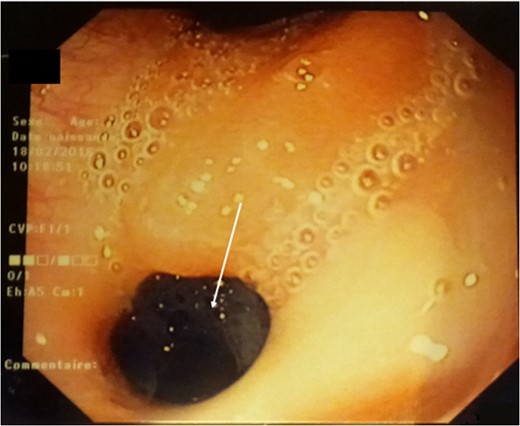

Fibroscopy: a 5-mm fistulous hole on the high part of the stomach.